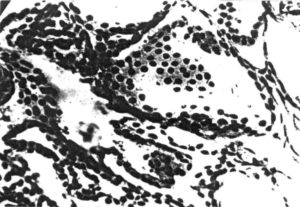

Наиболее опасной считается предраковая пролиферация желудочной стенки, когда начинает умножаться количество темных вытянутых клеток в зоне шеек желез желудка.

В самом начале процесс несет регенеративный характер, но из-за нарушенной дифференцировки клеток полного восстановления слизистой не наблюдается. Железы в результате покрываются несвойственными ими темными вытянутыми клетками, которые в норме находятся лишь в шейках этих желез. В дальнейшем это приводит к развитию злокачественного образования – карциномы.